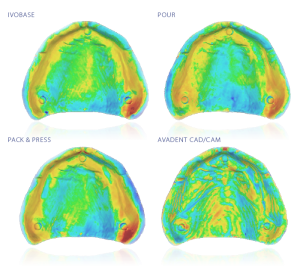

COMPARING THE SURFACE MATCHING ACCURACY OF DENTURES

B. Goodacre DDS. Loma Linda University School of Dentistry.

Complete dentures can be processed using a variety of techniques. The ultimate goal of each technique is to produce a completed prosthesis that exhibits retention, stability, and support through minimal amounts of processing distortions.

Published in “The Journal of Prosthetic Dentistry“